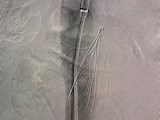

介入助力 巧取滤器丨中南大学湘雅二医院桂林医院成功开展疑难复杂下腔静脉滤器取出术

近日,中南大学湘雅二医院桂林医院胃肠、肛肠、血管外科成功救治一名因下腔静脉滤器严重变形、回收钩贴壁,随时有生命危险的43岁患者,挽救了患者的生命。一波三折,小小滤器难取出患者滤器造影图患者徐先生3个月前出现左下肢肿胀,当地医院诊断下肢静脉血栓形成,为了预防致死...